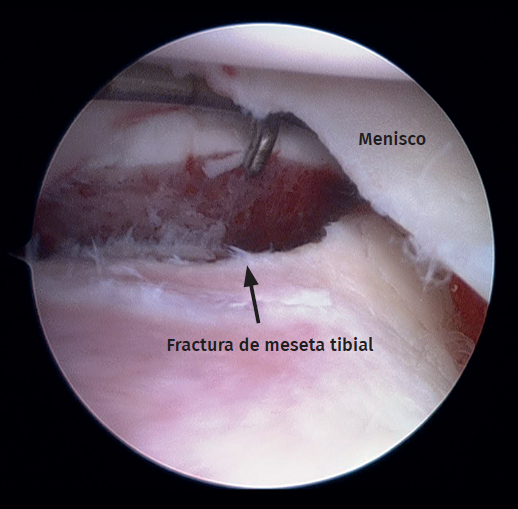

Figure 2. Right knee, Schatzker II tibial plateau fracture. Step-off arthroscopic view from the anteromedial portal. Probe placed in the anterolateral portal.

Standard anterolateral and anteromedial portals are created adjacent to the patellar tendon and the joint is visualized with a 30° arthroscope while the knee is insufflated with normal saline. A diagnostic arthroscopy is performed to confirm the TPF, the step-off and the presence of associated lesions (Figure 2). An arthroscopic shaver is inserted into the knee to clear the debris and improve visualization. Next, a small longitudinal anterolateral skin approach is performed, and the fractures are fixed with cancellous screws and/or a buttress plate applied on the external side (minimally invasive plate osteosynthesis), according to the type of fracture diagnosed (Figure 3). Arthroscopy is used to assist reduction and, when needed, to treat soft tissue injuries. The senior authors prefer to perform meniscal repair or partial meniscectomy before bone fixation due to the better visualization of the meniscus. Conversely, ligamentous reconstructions are performed after arthroscopically assisted fixation to ensure bony stability.

Meniscal tears were the most frequent soft tissue lesion (Figure 4), noted in 26 of the 40 patients evaluated (65.0%). The highest meniscal tear rate was seen in type II tibial plateau fractures (type I: 15.3%; type II: 80.7%; type III: 4%). Table 1 shows the number of meniscal injuries for each fracture type.

Figure 4. Left knee. View from the anterolateral portal. Peripheral longitudinal tear involving the lateral meniscus body.